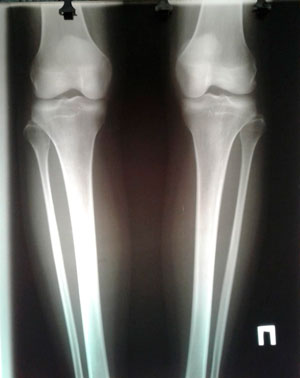

Исходник - 29 лет.

Дата операции - 12.08.2019.

Ротация с обеих сторон.